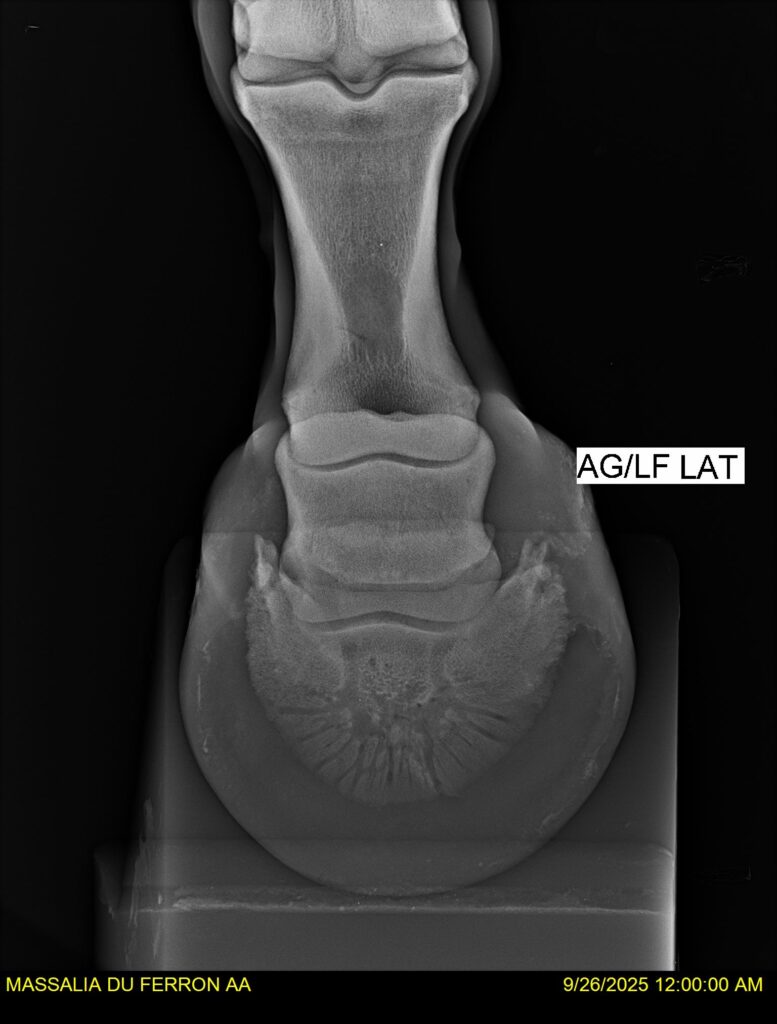

MASSALIA DU FERRON, jument qui prendra 4 ans par PRESTIGE KALONE x TRESOR DU RENOM. Un mental en or et un véritable sens de la barre ! Facile d’accès ! Bonne énergie et bons moyens. Souche moderne et très intéressante. Transport OK, maréchalerie OK, santé RAS, Bilan clichés radios OK.

RADIOS et COMPTE RENDU